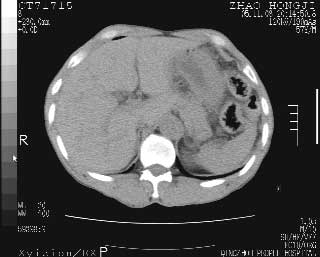

临床资料:男性,57岁,上腹部疼痛并5天,突然加重并延及全腹伴恶心5小时入院。胰淀粉酶化验在正常范围。检查:腹肌紧张,全腹压痛、反跳痛,尤以右上腹部为著。肠鸣音减低。血常规:wbc14.6x10/9, n:11.3x10/9 ,血压:135/90mmhg. 胸部透视:腹部肠腔轻度张气,未见其它异常改变。

肝缘见少许气体,胰尾部见少许气体包饶(蓝色圈),12指肠上部或球部邻近胆囊周边也可见少许气体影(黄色圈),并忖托出胆囊壁,12指肠远段肠道内未见明显气体(白色箭)。

肝脏前缘见少量积气、胰尾部见少许气体包饶,肾前筋膜未见增厚,临床淀粉酶不高,意见:上消化道穿孔。

入院3小时后行剖腹探查术,见腹腔内大量脓性混浊液约1000ml,十二指肠球部溃疡穿孔,溃疡面约2.5x2cm,穿孔直径约0.6cm。胃内容物外益,周围组织炎性水肿明显。行十二指肠穿孔修补术。术后诊断:

1、十二指肠溃疡穿孔

2、弥漫性腹膜炎

对于少量的腹腔游离气体,ct检查较普通透视有绝对的优势,它不仅可以看到肝脏前上缘的气体,而且还能够看到小网膜区的游离气体。从而可以肯定诊断。各位分析战友的很好,感谢大家的参入!